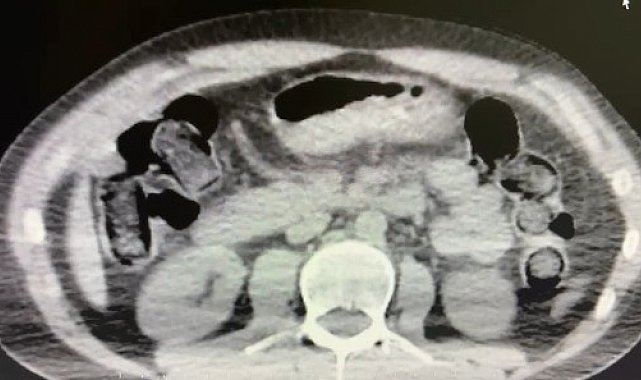

Nevşehir İl Emniyet Müdürlüğü Narkotik Suçlarla Mücadele Şube Müdürlüğü ekipleri, kentte uyuşturucu ve uyarıcı madde ticareti yapmak ve kullanmak suretiyle vatandaşları zehirleyen sokak satıcılarına yönelik çalışma başlattı. Cumhuriyet Başsavcılığı koordinesinde çalışmalarını yoğunlaştıran ekipler, şüpheliler S.B. ve O.R.'nin 'yutma yöntemi' ile kente uyuşturucu madde sevk edeceği bilgisi üzerine operasyon düzenledi. Şüphelilerin ikametlerinde ve araçlarında yapılan aramada 101 kapsül halinde 722 gram uyuşturucu madde, 1 adet hassas terazi, uyuşturucu madde sevkiyatında yutma yönteminde kullanılan muhtelif materyaller, uyuşturucu madde ticaretinden elde edilen 20 bin 210 TL, bin 320 euro ve 10 ABD doları ele geçirildi. Emniyetteki işlemlerinin ardından adliyeye sevk edilen 2 şüpheli, çıkarıldıkları mahkemece tutuklanarak cezaevine gönderildi.